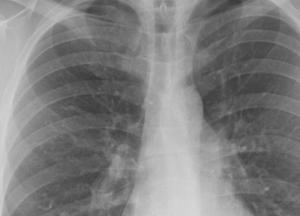

В Украине в 2020 году количество случаев активного туберкулеза снизилось на 30%, передает FaceNews.ua. Медики зарегистрировали свыше 17 тысяч случаев активного заболевания.

"В 2020 году в Украине зарегистрировали 17 593 случая заболевания активным туберкулезом, включая рецидивы. Это на 29,8% ниже, чем в 2019 году, тогда зарегистрировали 25 237 случаев", - говорится в сообщении ЦОЗ в Facebook..

Таким образом, в расчете на 100 тысяч населения показатель заболеваемости снизился с 60,1 до 42,2.

Дети до 17 лет в прошлом году стали меньше болеть туберкулезом на 32,1%.

В 2020 году уменьшилась на 35% заболеваемость туберкулезом в сочетании с ВИЧ/СПИДом. Было зафиксировано 2 860 случаев по сравнению с 4 398 случаями годом ранее.